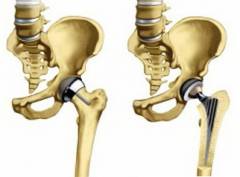

Это наиболее распространенный и эффективный метод лечения коксартроза II – III степени. Суть метода заключается в удалении суставных поверхностей обоих костей и замене их механическим суставом, который вживляется в тазовую и бедренную кость.

Механический сустав состоит из шарнира на ножке (аналог головки бедренной кости) и чашечки, аналогичной вертлужной впадине. Протез изготавливается из специального материала губчатой структуры, что обеспечивает большую стабильность в послеоперационный период. Вначале протез крепится к кости с помощью специального клея, но со временем костная ткань прорастает в поры протеза, сливаясь с ним.

Операция выполняется следующим образом: после общего наркоза удаляется головка бедренной кости, в самой кости сверлится отверстие для ножки протеза. В области вертлужной впадины также высверливается отверстие для чашечки протеза. Протезы крепятся к костям с помощью специального цемента, после чего соединяются. Обязательным этапом является проверка амплитуды движений в суставе. Если она не нарушена, производится ушивание раны, и операция завершается. Послеоперационный период схож с таковым после артропластики.